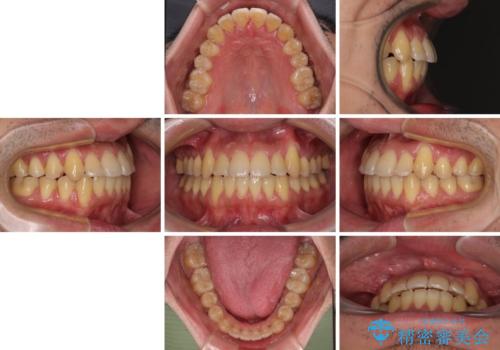

八重歯とクロスバイト 目立たないワイヤー装置で矯正治療

- 2年

- 10-30回

デコボコが解消されると歯列が拡大される方向に動くため、出っ歯のような仕上がりとなることがあります。舌の突出癖を改善するトレーニングをしっかりと行っていただくことで、突出を抑制することができます。